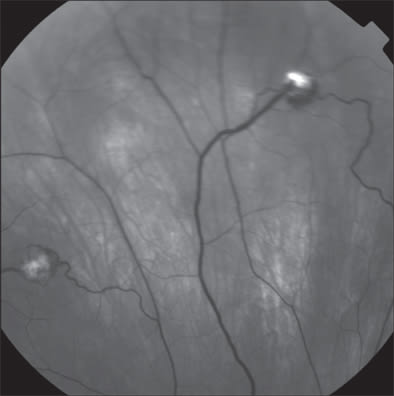

Ophthalmologic examination demonstrated a corrected visual acuity of 20/20 in each eye and the patient correctly identified 11/11 Ishihara color plates. Pupils were briskly reactive without any afferent defect. Slit-lamp examination of the anterior segment was unremarkable. Dilated funduscopic examination showed 3 midperipheral endophytic retinal hemangiomas in the right eye and 1 peripheral hemangioma in the left eye. Fluorescein angiography confirmed the presence of these retinal hemangiomas.

Figure 9. Midphase fluorescein angiography showing retinal hemangiomas in the right eye.

Figure 10. Another midphase fluorescein angiography showing retinal hemangiomas in the right eye.